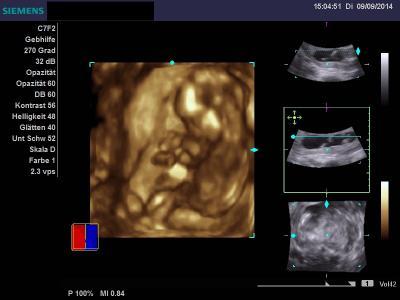

Allerdings wurde auch beim Ultraschall festgehalten, dass die Kindeslänge von 9,5 cm der 14+5 ssw entspricht ... *grübel*

anbei auch mal ein kleines Bildchen von unserem neuen Sonnenschein